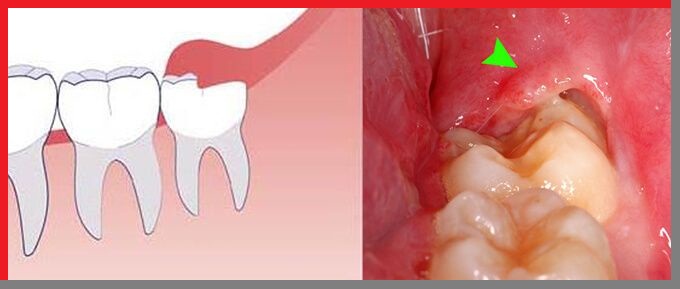

Đây là biến chứng xuất hiện khi răng khôn của bạn mọc bất thường: mọc lệch, mọc ngầm, mọc chéo,….Khi mắc bệnh lý này, bạn sẽ cảm thấy rất đau đớn, khó chịu và có thể bị sốt. Nếu không được điều trị kịp thời, bệnh có thể gây ra một số tác hại như:

Viêm lợi trùm là biến chứng xuất hiện khi răng khôn của bạn mọc bất thường